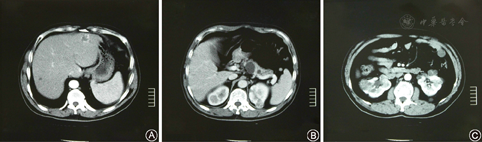

腹部CT检查(图4):肝内多个低密度灶,边界部分清楚、部分模糊,较大的两个病灶直径2.0 cm,增强后明显强化,胰腺内低密度灶较大者直径3.0 cm,无强化,双肾多个结节状异常密度影,部分呈囊性水样密度,部分病灶内有分隔、伴结节样改变,增强扫描条索分隔及结节影有强化,囊性病灶无强化。腹部MRI检查:双肾多个大小不等异常信号影,T1WI为不均匀低信号、T2WI为等高混杂信号影,增强为轻中度不均匀强化,左肝外侧段及右肝下部异常信号影,呈向心性渐进性强化,另双肾、胰腺、肝脏多个大小不等未见强化囊肿信号影。CT及MRI诊断:双肾多发肿瘤,肝多发血管瘤,双肾、肝、胰腺多发囊肿。

A.肝内多个低密度灶,边界部分清楚、部分模糊,增强后明显强化;B.胰腺内多个低密度灶较大直径3.0 cm,无强化;C.双肾多个结节状异常密度影,部分呈囊性水样密度,部分病灶内有分隔、伴结节样改变,增强扫描条索分隔及结节影有强化,囊性病灶无强化